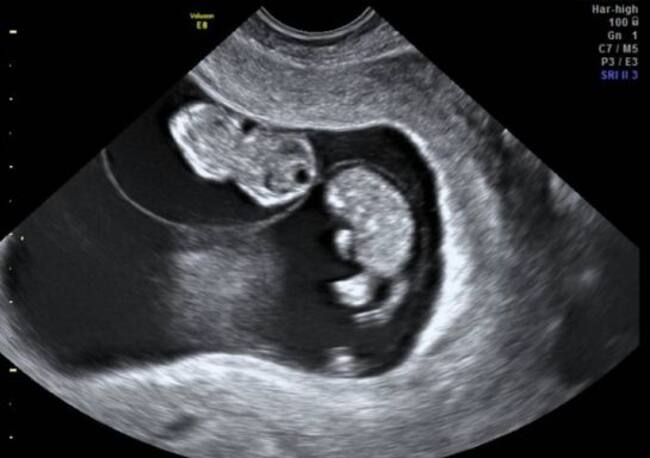

Nuevo caso de mellizos por superfecundación heteropaternal en China, ultrasonido / W Radio